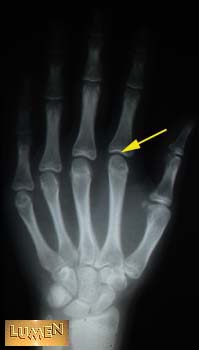

18. What type of joint is found here?

Condyloid.